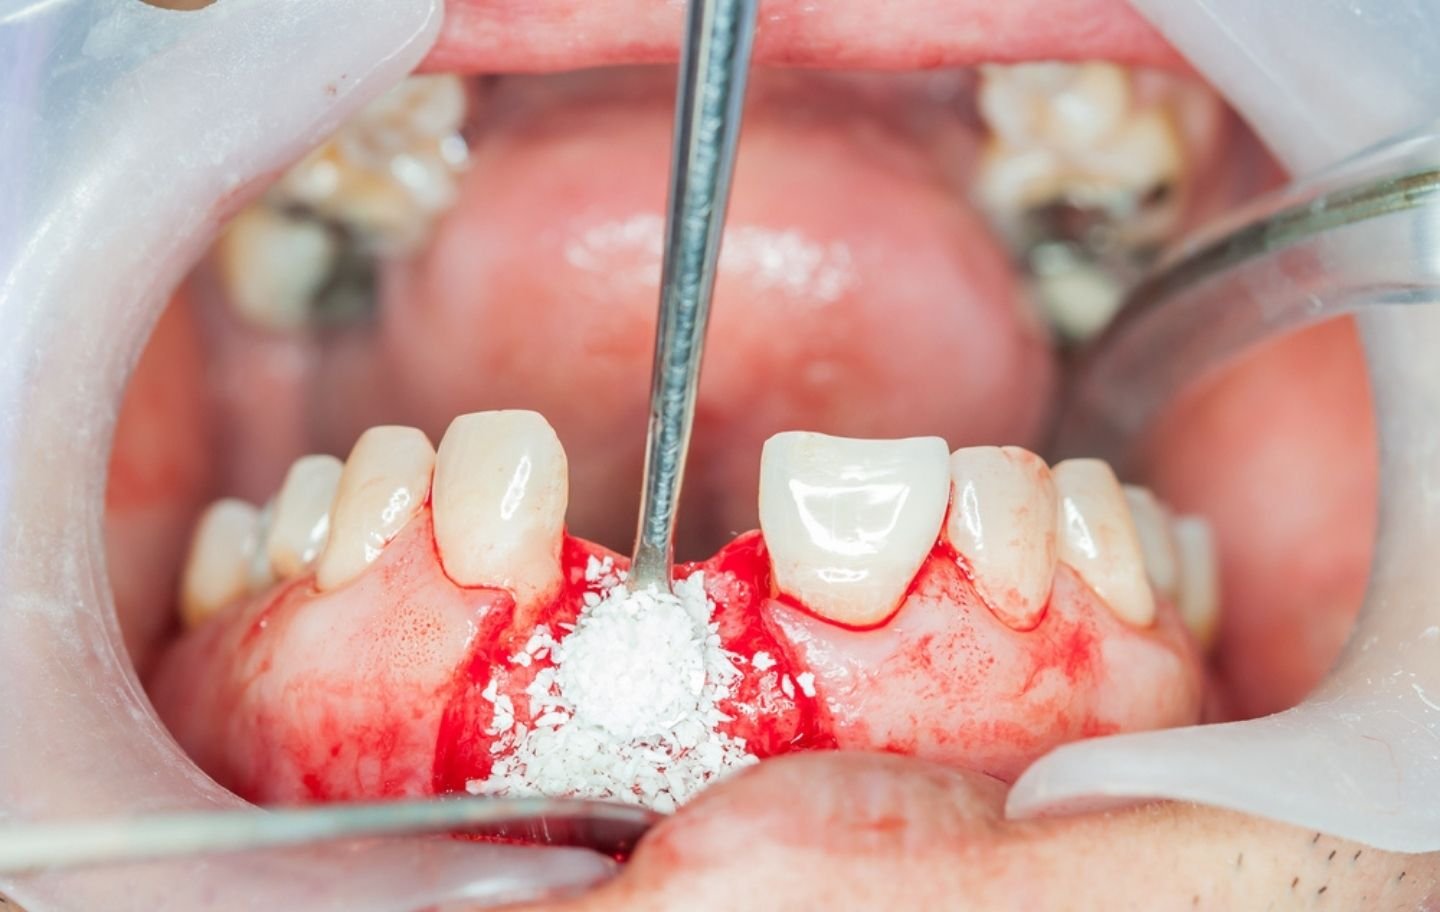

2️⃣ Bone Grafting Surgery

- Local anesthesia or sedation is applied for comfort.

- A small incision is made in the gum to access the bone.

- The graft material is placed and secured with a membrane or special proteins to enhance healing.

- The gum is sutured, and recovery instructions are given.